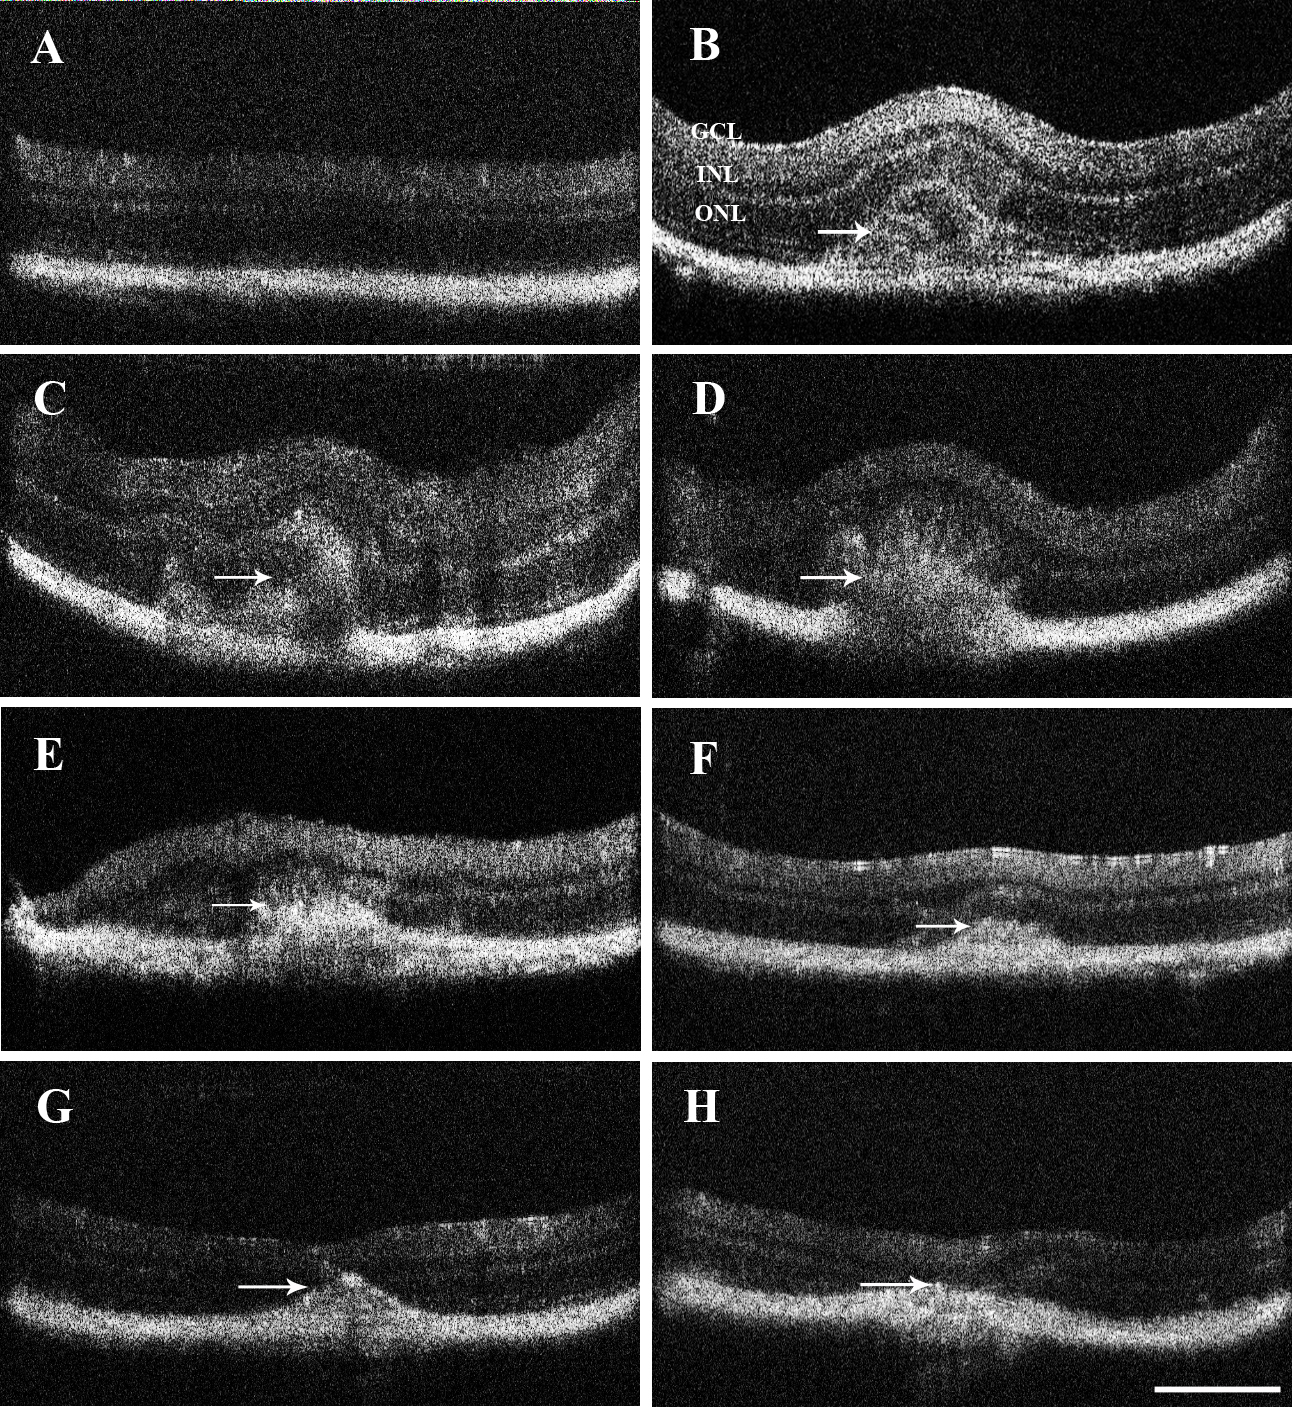

Figure 1. Cross-sectional spectral domain optical coherence tomography images for two groups of eyes over a time period of 3 weeks.

The images before the injection (A; n=10) and immediately after the injection (B; n=10) were followed up by scans at 3 days (C, D; n=30), 1 week (E, F; n=30), and 3 weeks (G, H; n=30). The Cyclosporin A (CsA) group (C, E, G; n=45) and the control group (D, F, H; n=45) showed the same trend in changes in the bleb: A distinct bleb with retinal detachment appeared immediately after cell

injection and after 3 days. One week after injection, the initial bleb settled down, but the retinal detachment space was

still evident (arrows in E, F). Three weeks after injection, the retina appeared normal without evident retinal detachment (arrows in G, H). The scale bar is 50 μm.